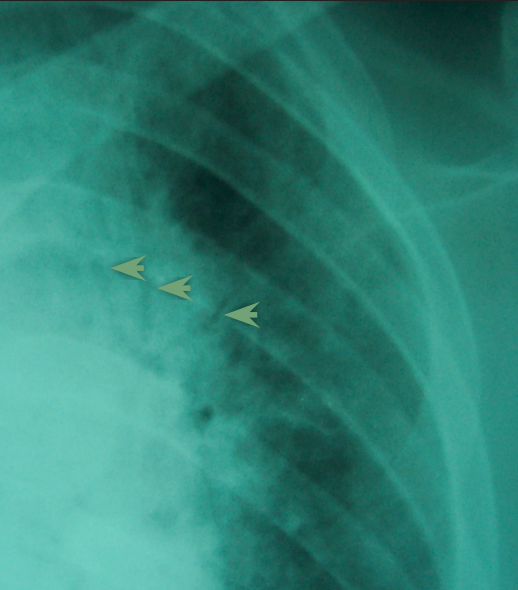

RTA patient with multiple rib fractures

discontinuity in ribs

multiple right sided rib fracture

subtle simple apical pneumothorax on right side

hemothrax in CP angle on right side

(rib fracture can be complicated by pneumothorax or hemothorax so always check)